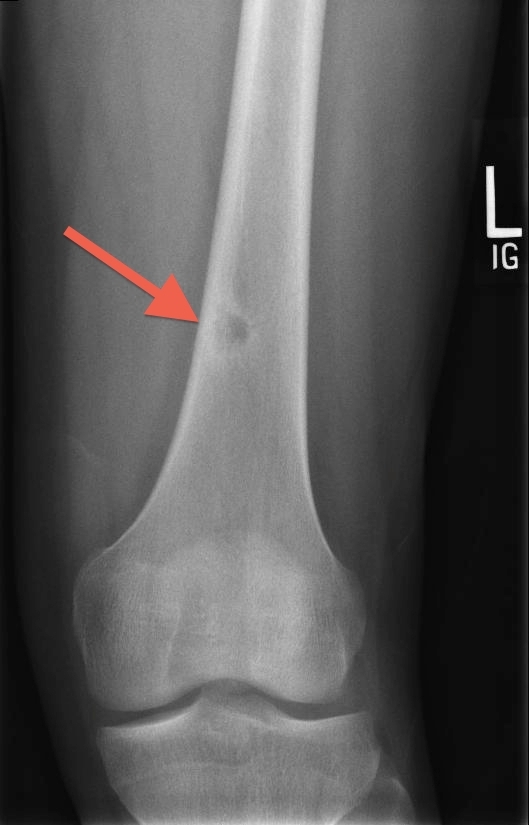

Giant Cell Tumor

This patient's x-ray findings of an expansile and eccentric lytic area ("soap-bubble" appearance) are highly suggestive of giant cell tumor of bone (GCTB). GCTB is a benign and locally aggressive skeletal neoplasm seen in young adults. Patients usually present with pain, swelling, and decreased range of joint motion at the involved site. Nearly 10%-35% of affected patients experience pathologic fractures due to thinning of the bone cortex in weight-bearing areas.

GCTB typically presents on x-ray of the epiphyseal regions of the long bones, most commonly the distal femur and proximal tibia around the knee joint. Magnetic resonance imaging can show the tumor containing both cystic and hemorrhagic regions. Pathology typically shows sheets of interspersed large osteoclast giant cells that appear as round-to-oval polygonal or elongated mononuclear cells. Surgery (eg, intralesional curettage with or without bone grafting) is first-line treatment for GCTB.